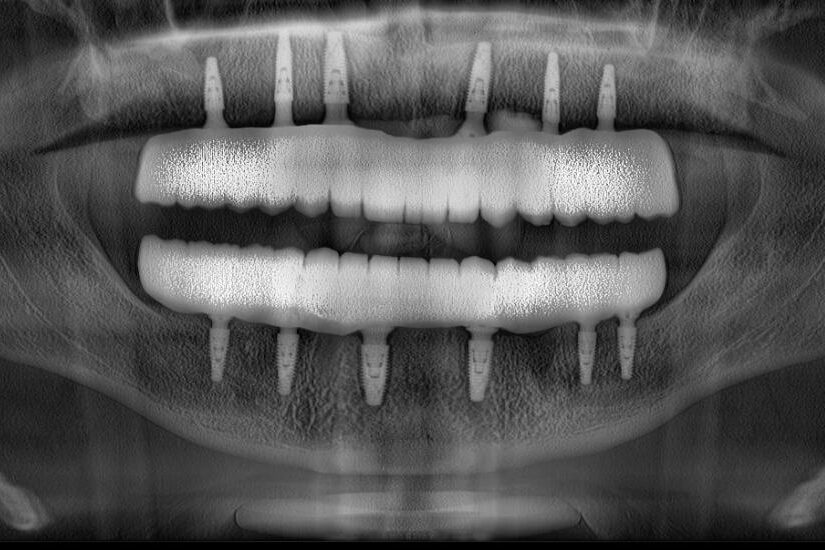

Mükemmeliyet odaklı yaklaşımı, ailesinin ve kıymetli hocalarının desteğiyle birleşerek Dr. Ademhan’ı cerrahi diş hekimliği alanında dikkat çeken bir kariyere taşımıştır. Mesleki uzmanlık alanları arasında dental implantlar, çene ameliyatları (ortognatik cerrahi), gömülü diş çekimleri, kemik greftleme ve yüz estetiği prosedürleri yer almaktadır. Cerrahi hassasiyeti, hasta odaklı yaklaşımıyla birleştirerek, fonksiyon ve estetiği birlikte sağlayan kişiye özel çözümler sunmasıyla tanınmaktadır.